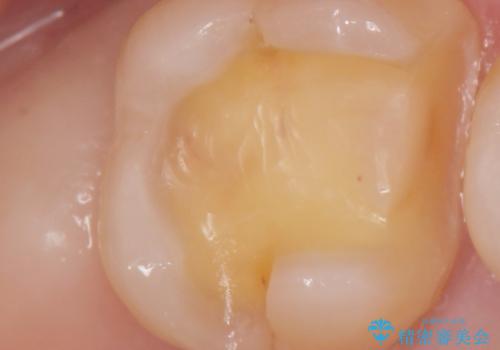

歯と歯の間の虫歯の治療。(コンタクトカリエス)

- メンテナンスで歯と歯の間に虫歯があったので拡大鏡下で虫歯を全て取り除き、e-maxインレーにて治療を行いました。